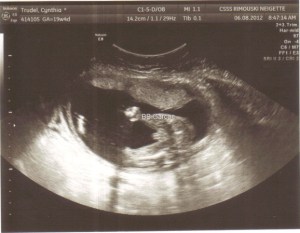

Bébé #2 à l’écho de mi-grossesse (6 août 2012)

Nous allions enfin savoir, à 22 semaines de grossesse (demain), si le petit coeur de bébé #2 est normal.

Bébé #2 est un beau petit garçon en parfaite santé. Son petit coeur est tout ce qu’il y a de plus normal et la doc nous a dit que, si c’est correct maintenant, ce l’est pour la vie dans son cas!